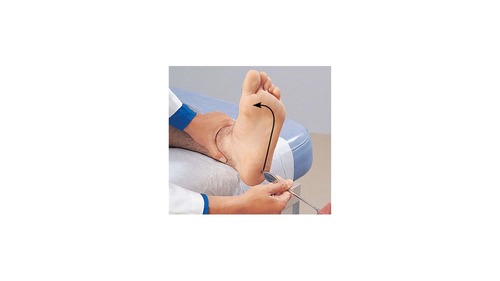

True or False: A positive babinski sign is normal in an adult.

false

If upon performing this test on an adult the toes are observed to flair this could indicate _____.

damage to the corticospinal tract